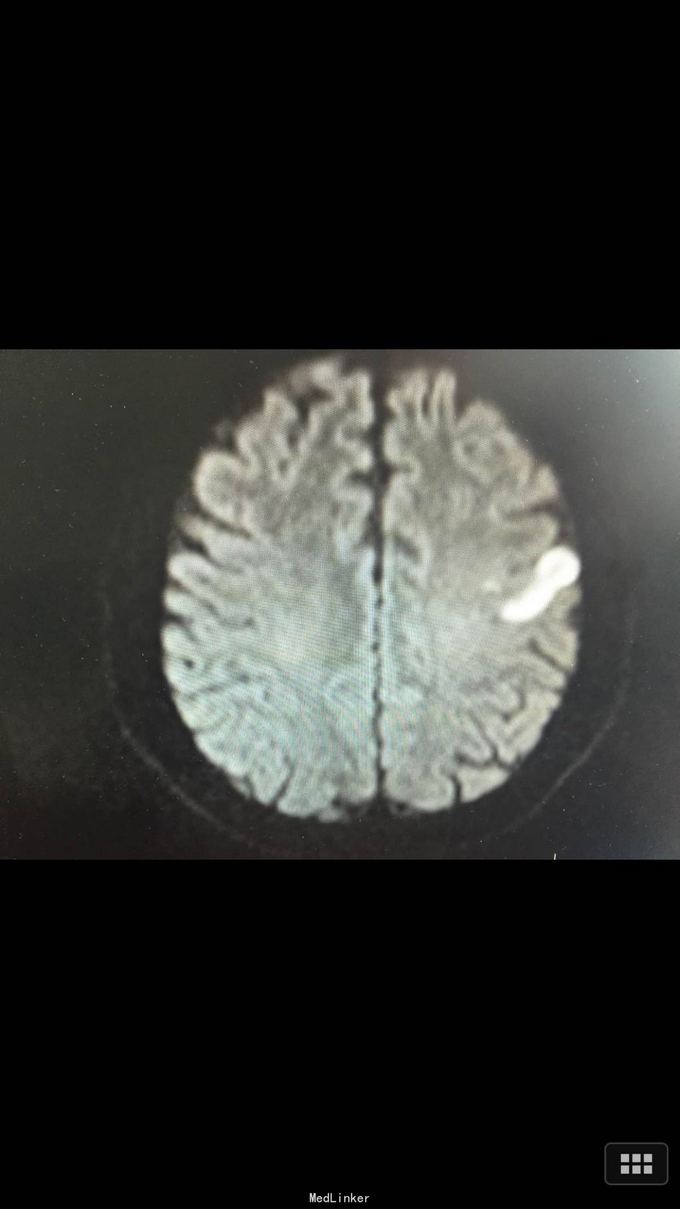

查体:BP:140/100mmHg,心肺腹无异常,神志清醒,完全运动性失语,右侧中枢性面瘫,四肢肌力、肌张力正常,腱反射正常,巴氏征R-L-,左足弓形足。 化验:血糖:14.3mmol/l,血脂:总胆固醇:13.29mm0l/l,LDL:6.6mmol/l,甘油三酯:24.51mmol/l。 影像学: